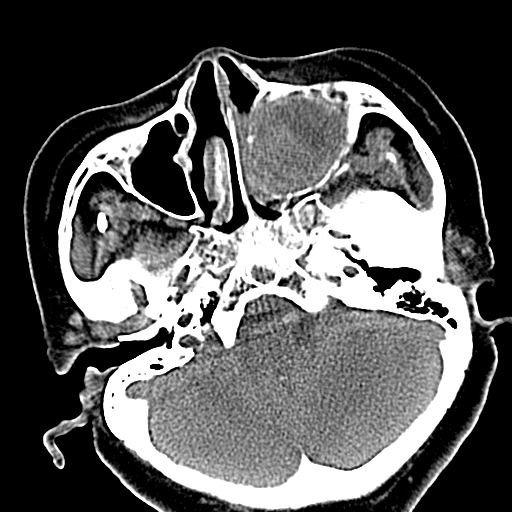

标题: CT19708:单侧上颌窦病变 [打印本页]

标题: CT19708:单侧上颌窦病变

老年患者,女。鼻塞多年。

考虑右侧上颌窦良性占位性病变,粘液囊肿可能性大;建议活检。

膨胀性生长,且骨质无破坏,说明时间久,良性;从密度,边缘看,内部还见坏死区,应该是实性肿瘤,定性,影像学无绝对的特异性

病灶密度很不均匀,骨壁膨胀中有断裂,考虑内翻乳头状瘤可能性大,粘液囊肿不排除

膨胀性生长,且骨质无破坏,说明时间久,良性;从密度,边缘看,内部还见坏死区,应该是实性肿瘤,定性,影像学无绝对的特异性,考虑内翻性乳头状瘤可能